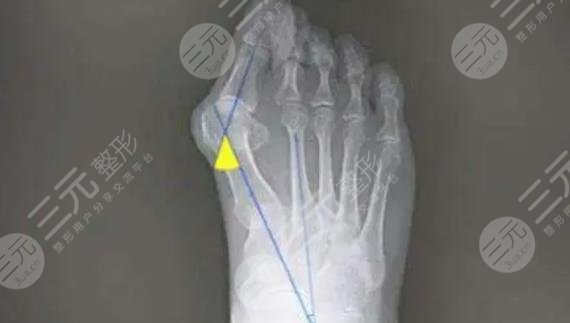

蘇敬達醫(yī)生所開展的大腳骨手術(shù),是以微創(chuàng)的手術(shù)方式所開展,術(shù)中借助于可移動的骨骼透視系統(tǒng)進行實時成像操作,所以準確度相對較高,可以有效的減少手術(shù)中的損傷,為愛美者美化足型的同時,穿鞋走路更加輕松!無需住院,隨治隨走,讓每位愛美人士都能滿足和體驗人性化的美足服務!實際手術(shù)中也是能夠依據(jù)顧客實際的足部情況,美學標準進行手術(shù)方案的設計,可實施性強,術(shù)后足部線條更為流暢和纖細!

目前臨床上針對于大腳骨的手術(shù)方式是比較多的,微創(chuàng)大腳骨的手術(shù)方式主要是以微創(chuàng)的方式進行剝離,手術(shù)創(chuàng)口只有針眼大小,手術(shù)操作期間也是有專業(yè)的成像設備提供直視化的操作,整個剝離過程對于神經(jīng)、組織損傷較小,另外在分離腳骨的同時,還能更好的幫助矯正受術(shù)者的腳型,術(shù)后只要做好加壓包扎,一般都是可以收獲比較滿意的足型效果,所以目前微創(chuàng)祛大腳骨手術(shù)方式是很受歡迎的!臨床反饋效果也比較好!該類手術(shù)是處于骨科手術(shù),也可以劃分為外科手術(shù),手術(shù)操作多是在局麻下進行,操作時長因大腳骨的難以程度而定!建議愛美者選擇正規(guī)的醫(yī)院開展手此類手術(shù)!